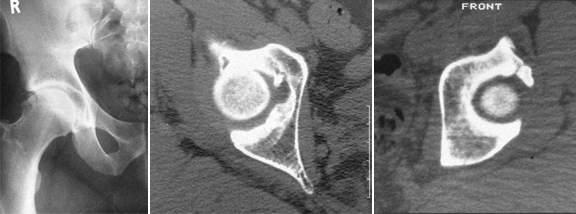

Na displasia da anca ou doença displásica da anca (DDA) o acetábulo é oblíquo, pouco profundo, estreito, lateralizado, antevertido e com deficiente cobertura anterosuperior.

O fémur tem cabeça pequena, colo curto, anteversão exagerada do colo, ângulo cervicofiafisário aumentado, desvio posterior do grande trocanter, canal femoral estreito.

OS EXAMES MAIS ÚTEIS PARA O DIAGNÓSTICO, são:

RX: face correcta da bacia, Rx de face e perfil das ancas

TAC